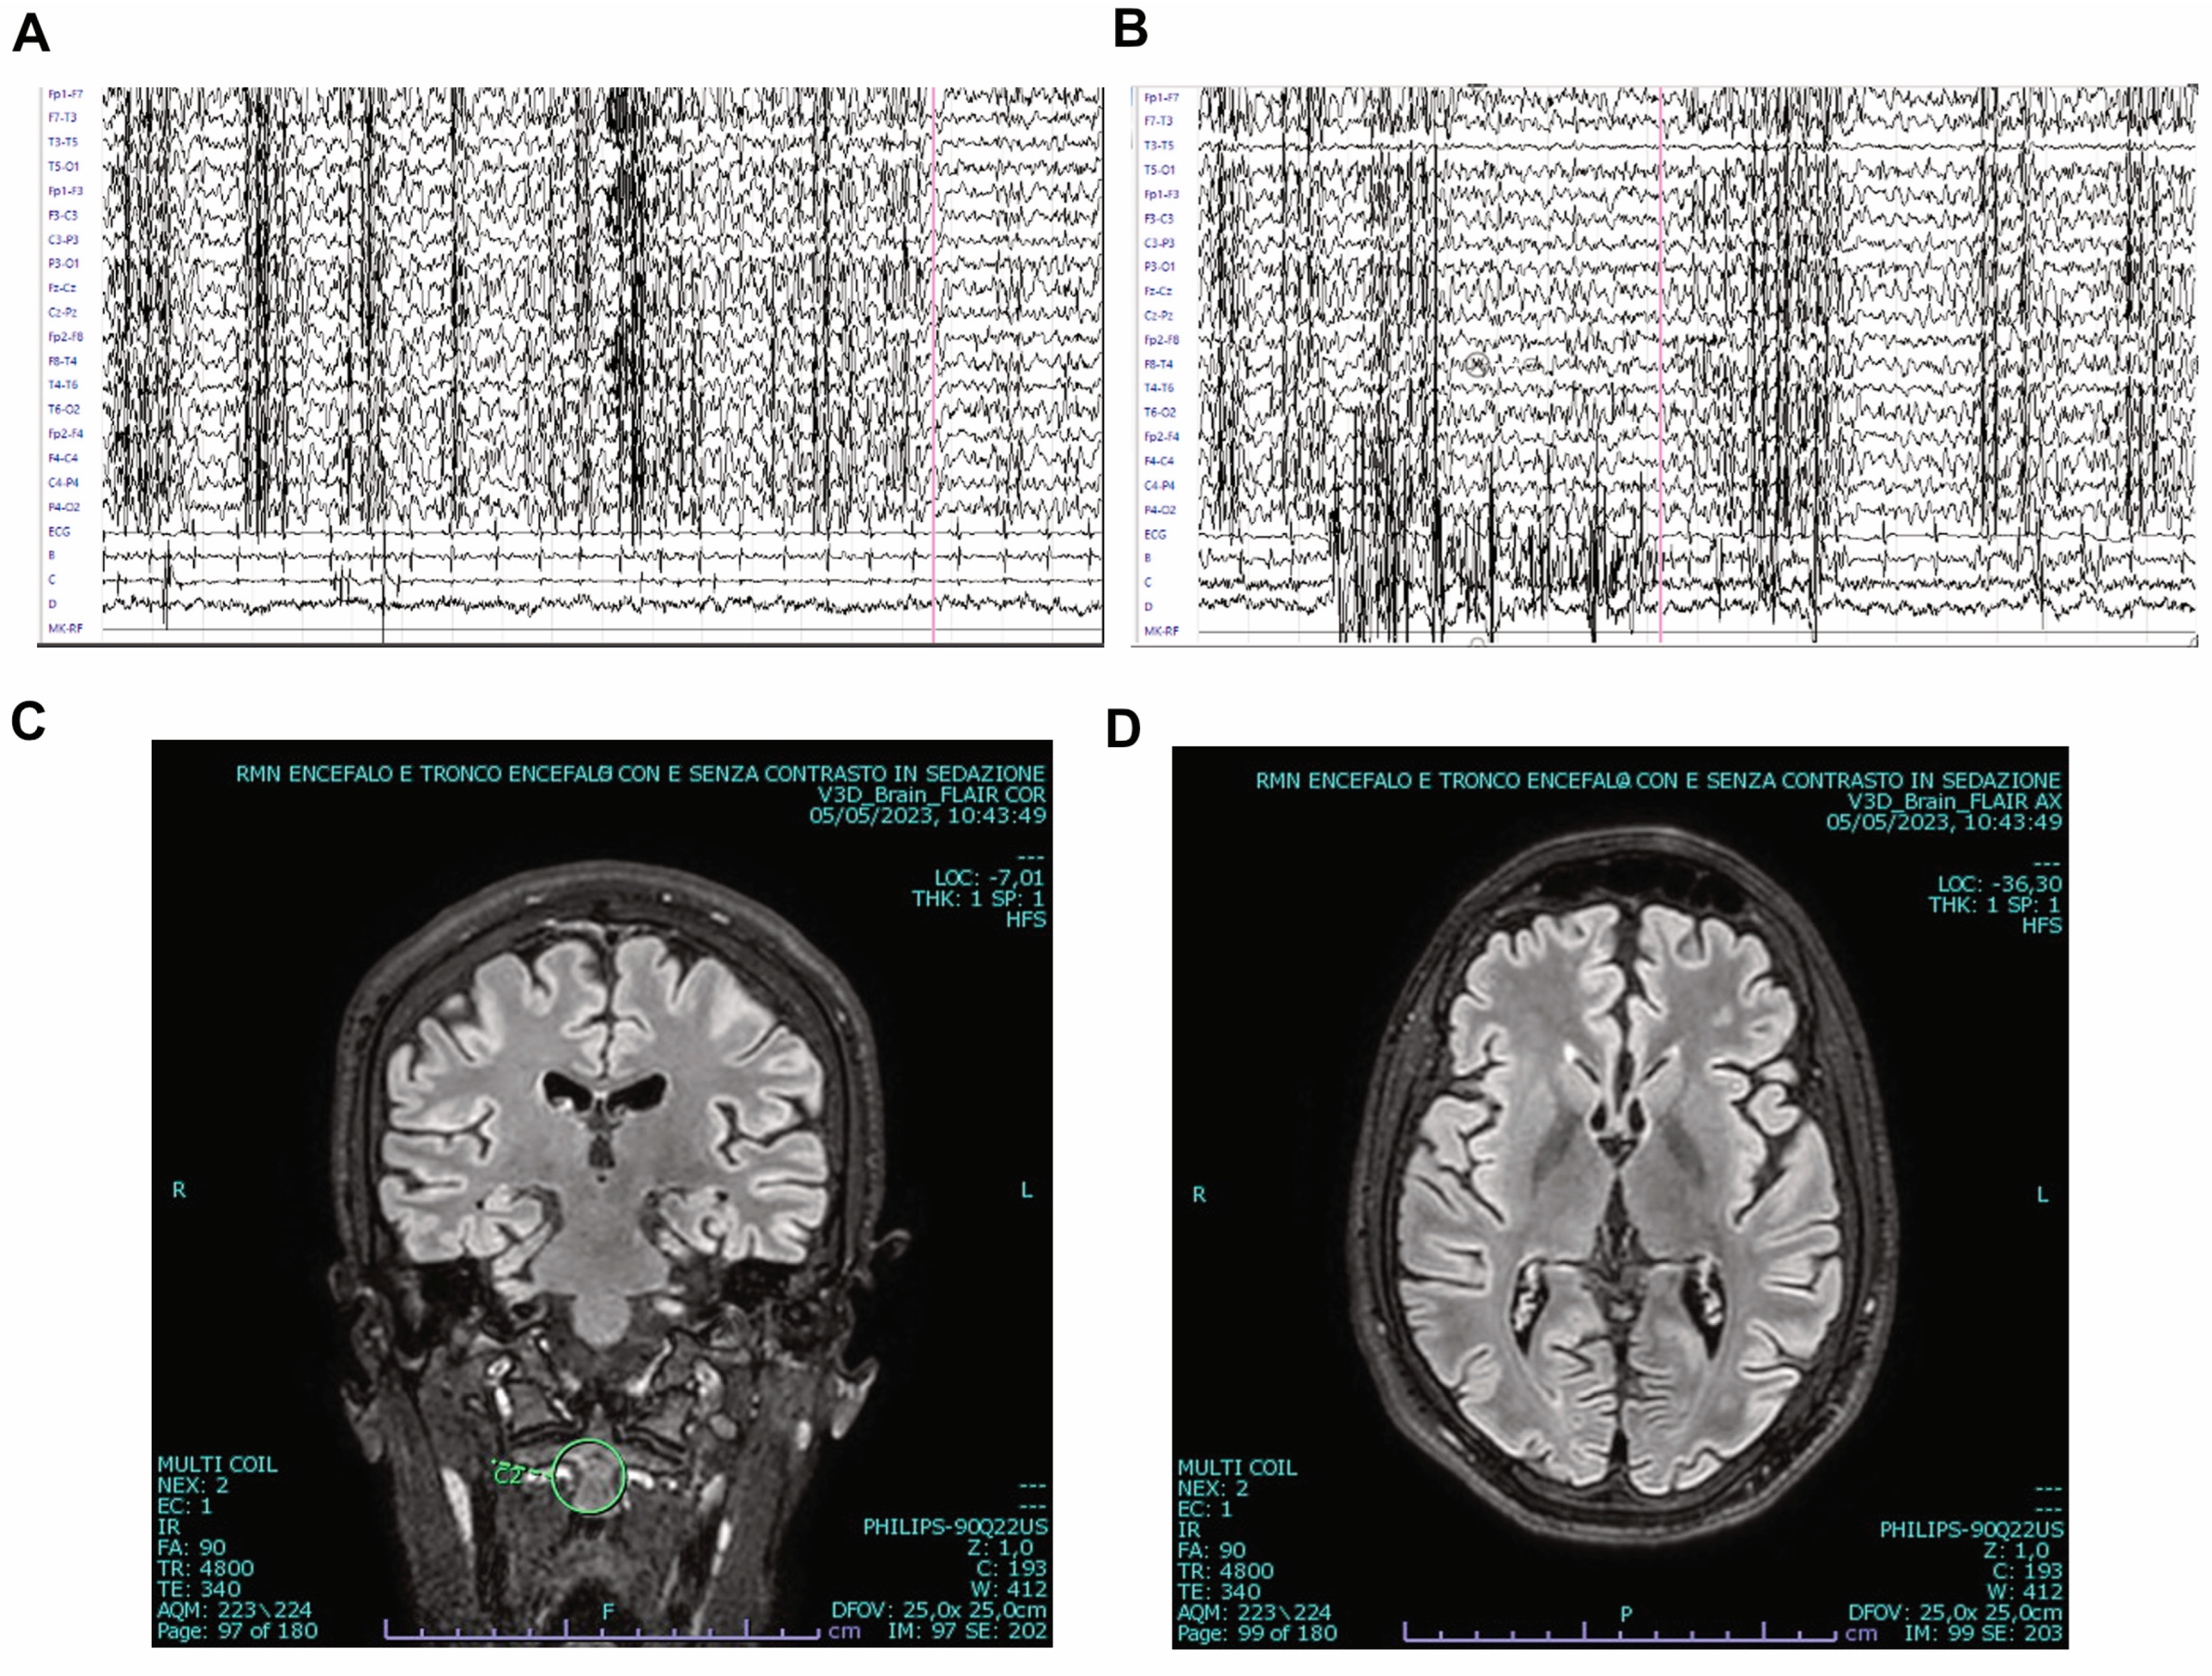

2. Patient and Methods

3. Results